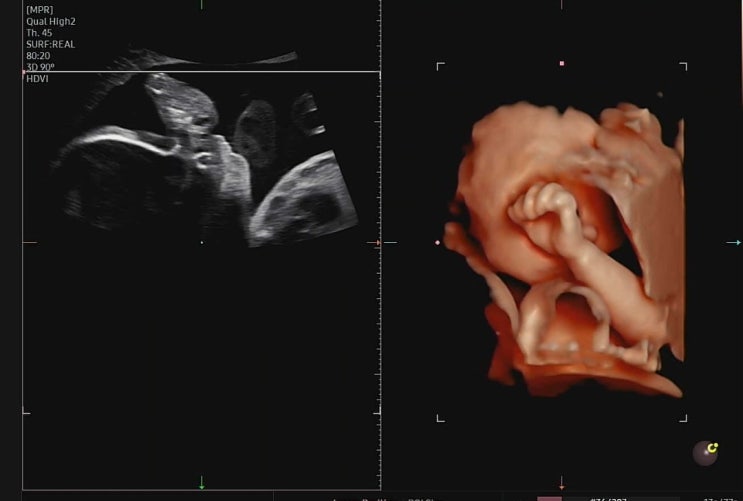

포항여성병원 26주 입체초음파 후기, 비용

임신하면서 제일 궁금했던 입체초음파! 초음파 사진을 좀 더 입체적으로 봐서 드디어 인간 같기도 하고, 누...